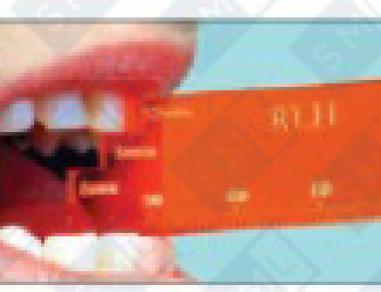

• Autoclavable Snore Screen identifies patient’s optimum airway zone

• Mandibular Positioning Simulators (MPS) determine a comfortable starting position for the bite registration. The 15-piece kit facilitates measurement in over 50 anterior plane positions – from habitual occlusion to 7mm anterior of edge-to-edge, combined with a vertical plane of 4—12 mm in 2mm increments